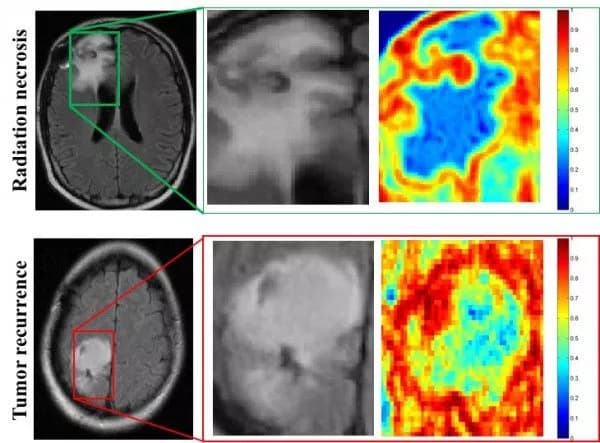

The program was nearly twice as accurate as two neuroradiologists in determining whether abnormal tissue seen on magnetic resonance images (MRI) were dead brain cells caused by radiation, called radiation necrosis, or if brain cancer had returned.

"One of the biggest challenges with the evaluation of brain tumor treatment is distinguishing between the confounding effects of radiation and cancer recurrence," said Pallavi Tiwari, assistant professor of biomedical engineering at Case Western Reserve and leader of the study. "On an MRI, they look very similar."

"What the algorithms see that the radiologists don't are the subtle differences in quantitative measurements of tumor heterogeneity and breakdown in microarchitecture on MRI, which are higher for tumor recurrence," said Tiwari, who was appointed to the Department of Biomedical Engineering by the Case Western Reserve School of Medicine.

More specifically, while the physicians use the intensity of pixels on MRI scans as a guide, the computer looks at the edges of each pixel, explained Anant Madabhushi, F. Alex Nason professor II of biomedical engineering at Case Western Reserve, and study co-author.

"If the edges all point to the same direction, the architecture is preserved," said Madabhushi, who also directs the Center of Computational Imaging and Personalized Diagnostics at CWRU. "If they point in different directions, the architecture is disrupted -- the entropy, or disorder, and heterogeneity are higher. "

In the direct comparison, two physicians and the computer program analyzed MRI scans from 15 patients from University of Texas Southwest Medical Center. One neuroradiologist diagnosed seven patients correctly, and the second physician correctly diagnosed eight patients. The computer program was correct on 12 of the 15.